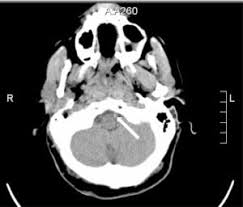

Reference - ASAACCFAHA guideline on the management of patients with extracranial carotid and vertebral artery disease mnh 21471149 p aph 59955487 p a9h 59955487 p byh 59955487 p beh 59955487 p bmh 59955487 p cxh 59955487 p mdc 21471149 p Vasc Med. However data on the treatment of posterior circulation stroke are less clear. SUMMARY Ten patients with angiographically verified occlusion of the basilar or vertebral artery have been followed for an average of 275 years. Occlusion of the Vertebral or Basilar Artery Follow Up Analysis of Some Patients with Benign Outcome Louis R. Variable restenosis rates have been reported in the literature with small improvements demonstrated using drug eluting stents. Endovascular treatment of vertebral artery stenosis VAS is a safe and effective technique for treating symptoms caused by posterior circulation ischemia with high technical and clinical success rates low complication rates and durable long-term results. Clinicians must carefully balance the risks of surgery versus the limitations of endoluminal intervention before proceeding.